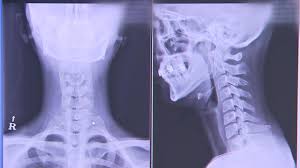

인간의 경추는 원래 머리의 무게와 외부 충격을 고르게 분산시키기 위해 C자 모양을 가지고 있습니다. 그러나 일상적으로 쪼그려 앉거나 머리를 뻗은 상태에서 전자기기를 사용하면 목뼈가 갈매기 모양으로 변형될 수 있습니다.

이러한 상태를 일자목증후군이라고 하며, 목의 곡률이 올바르게 형성되지 않아 목의 불편함과 통증을 초래할 수 있습니다.

3. 일자목증후군